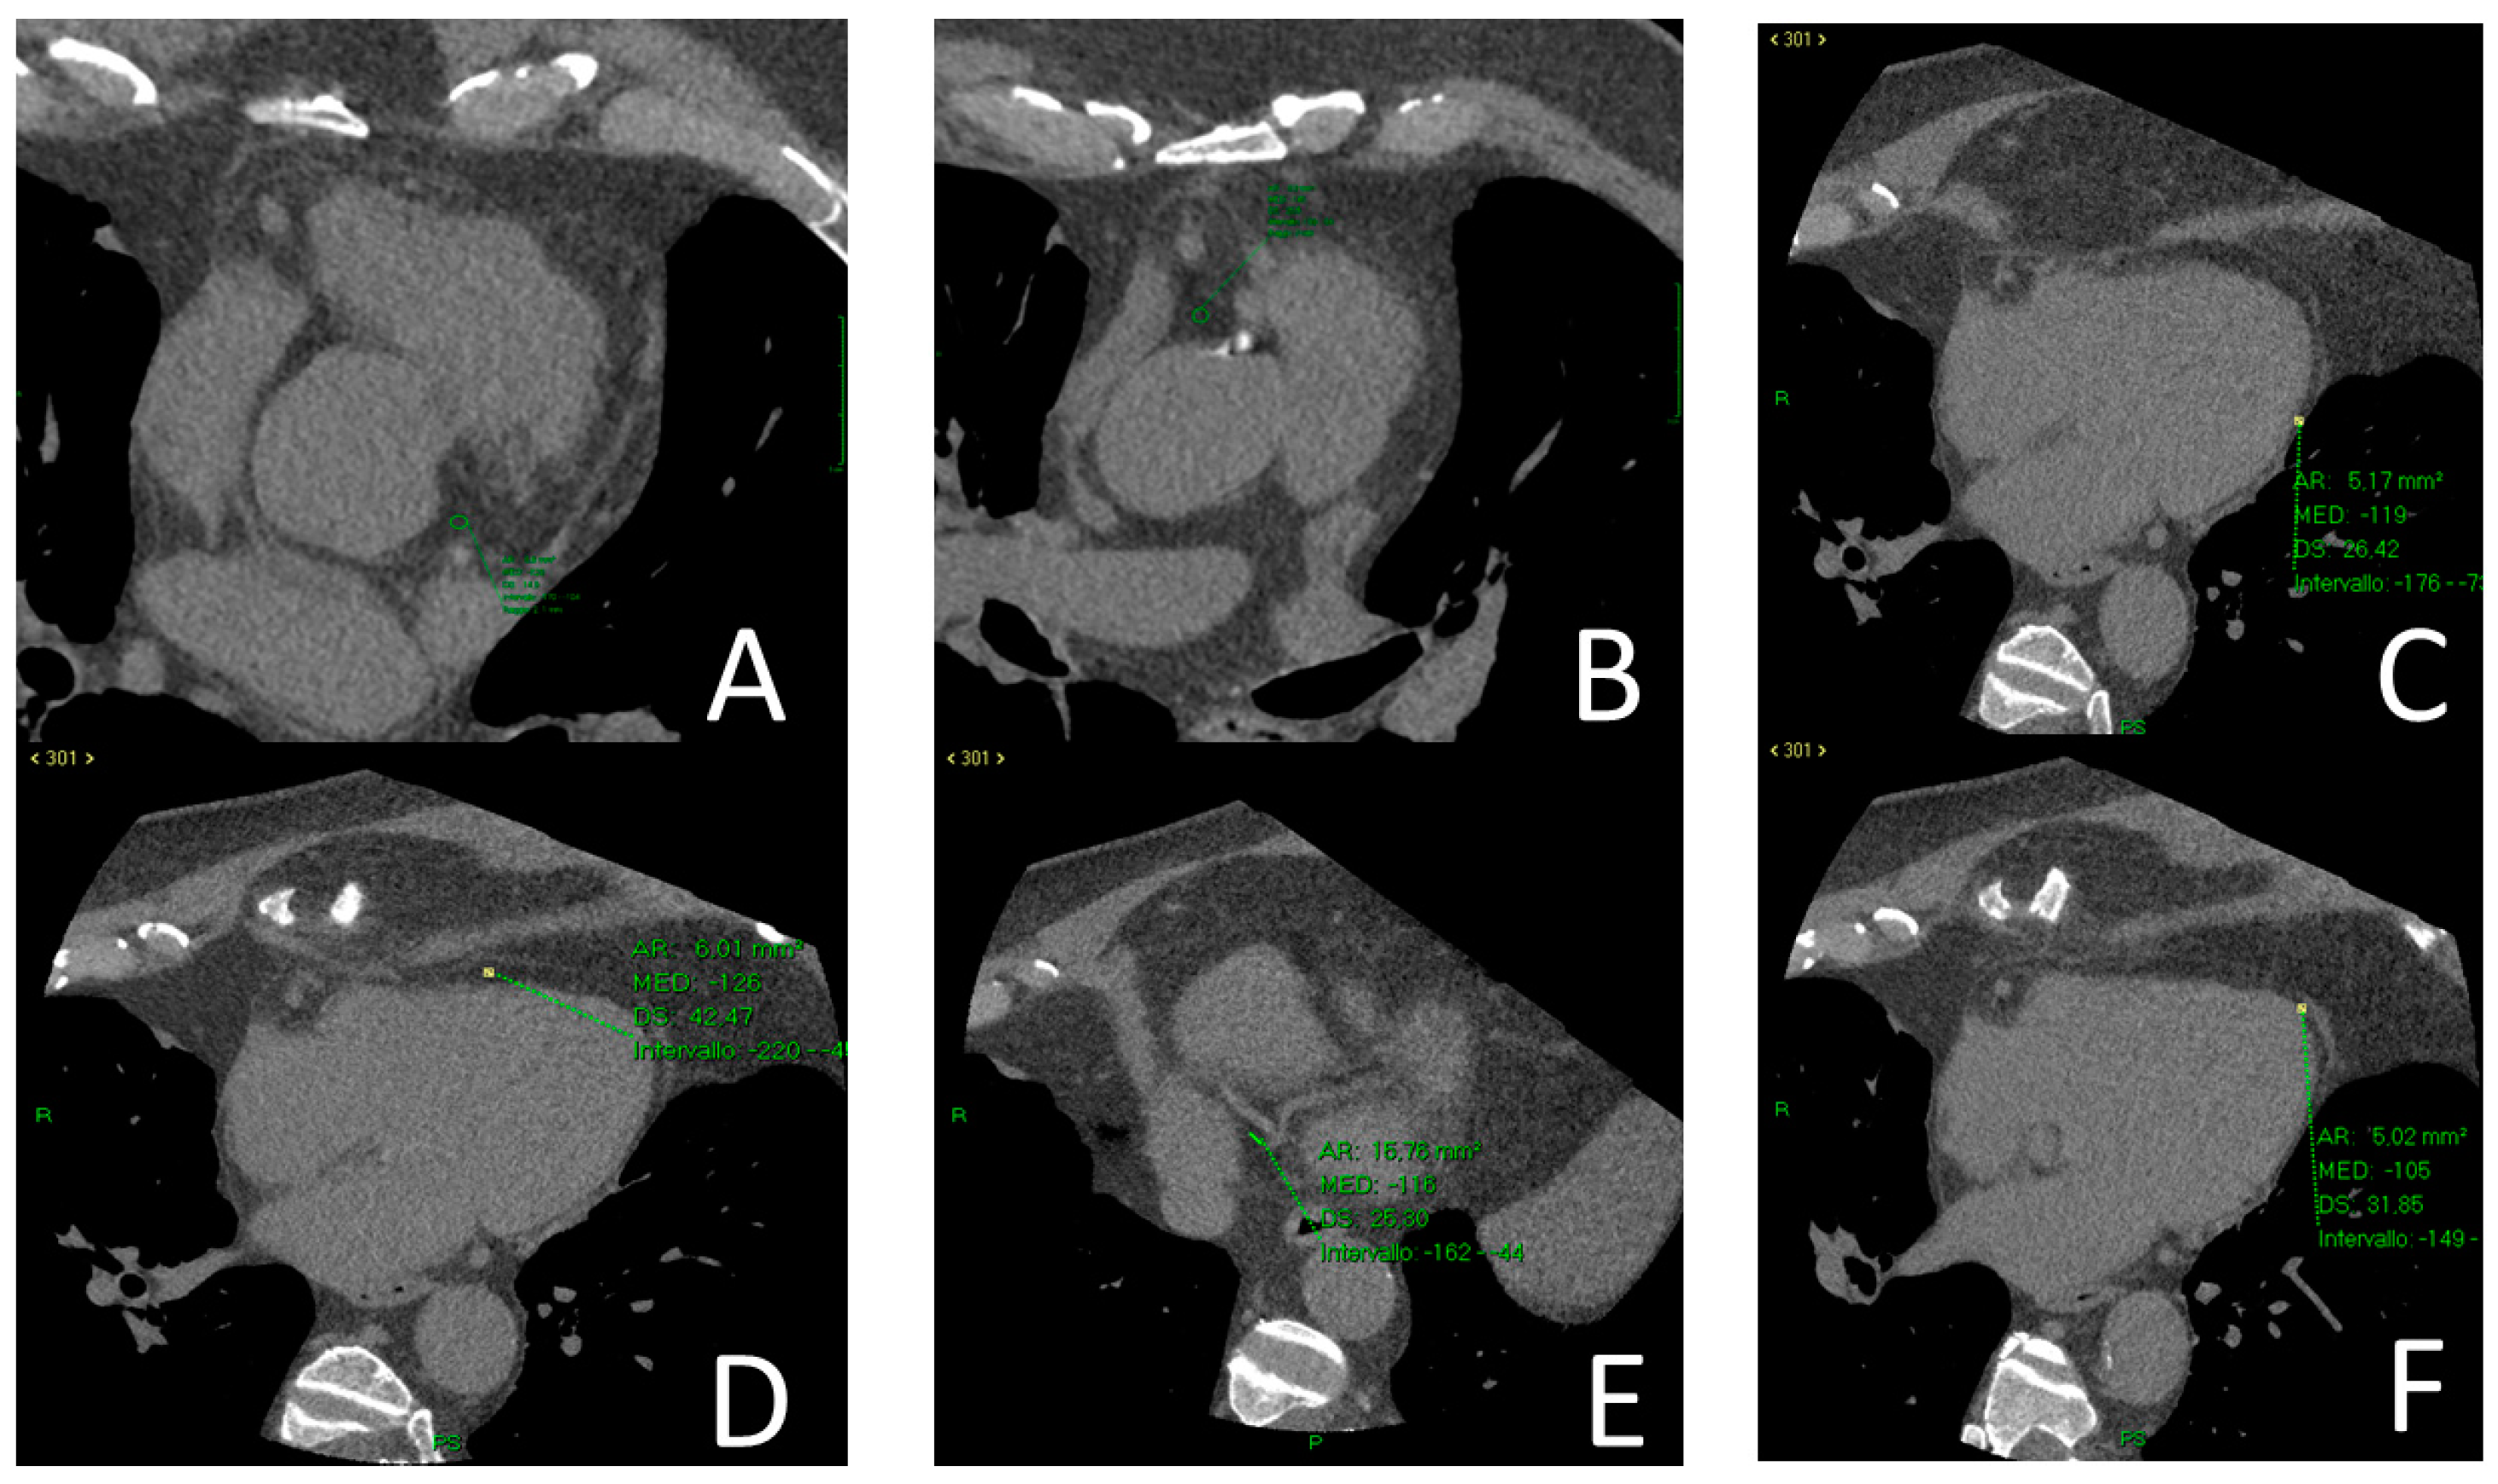

2.5. Epicardial Adipose Tissue Density

2.6. Cardiac Function